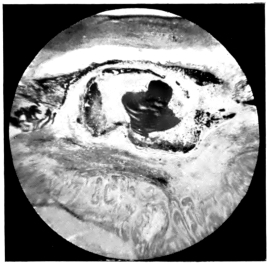

PLATE III.

16.

ABUNDANT EXUDATE INTO VITREOUS CAVITY

curly bracket span

42

17.

LENS FIRMLY FIXED BY ORGANIZED EXUDATE

18.

LENS FIRMLY FIXED BY ORGANIZED EXUDATE, BUT IN UNUSUAL POSITION

19.

TOTAL DETACHMENT OF RETINA, WITH CYST FORMATION

20.

RECLINED LENS LYING IN FRONT OF THE HYALOID BODY

21.

RECLINED LENS LYING IN FRONT OF THE HYALOID BODYxii